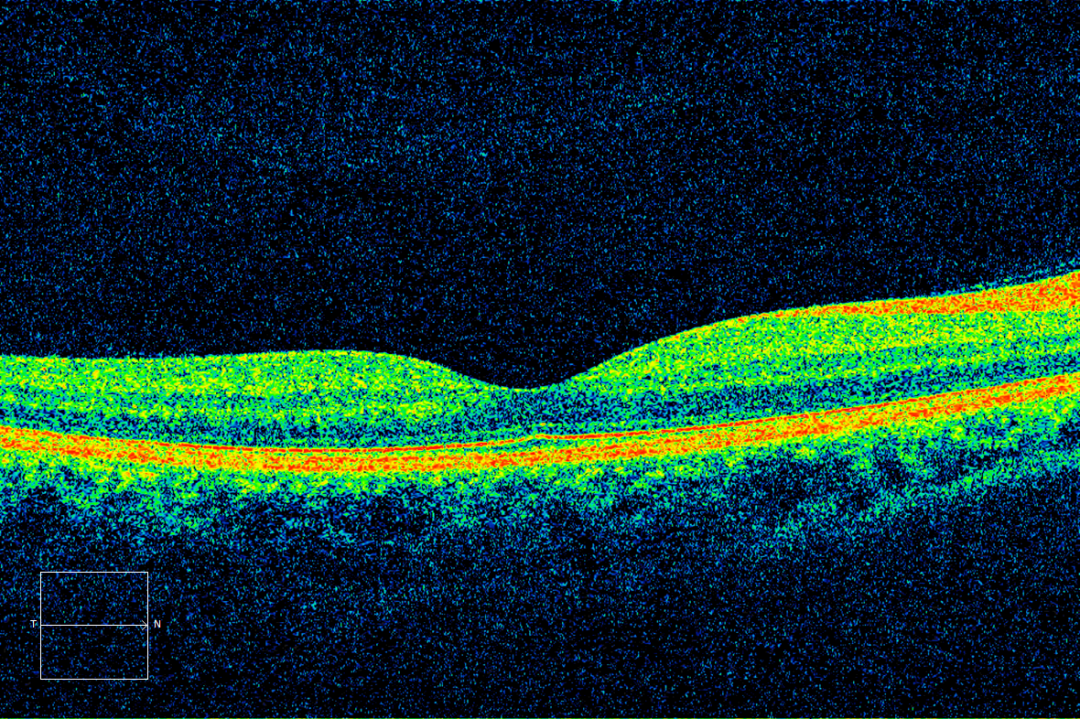

德国蔡司血流OCT